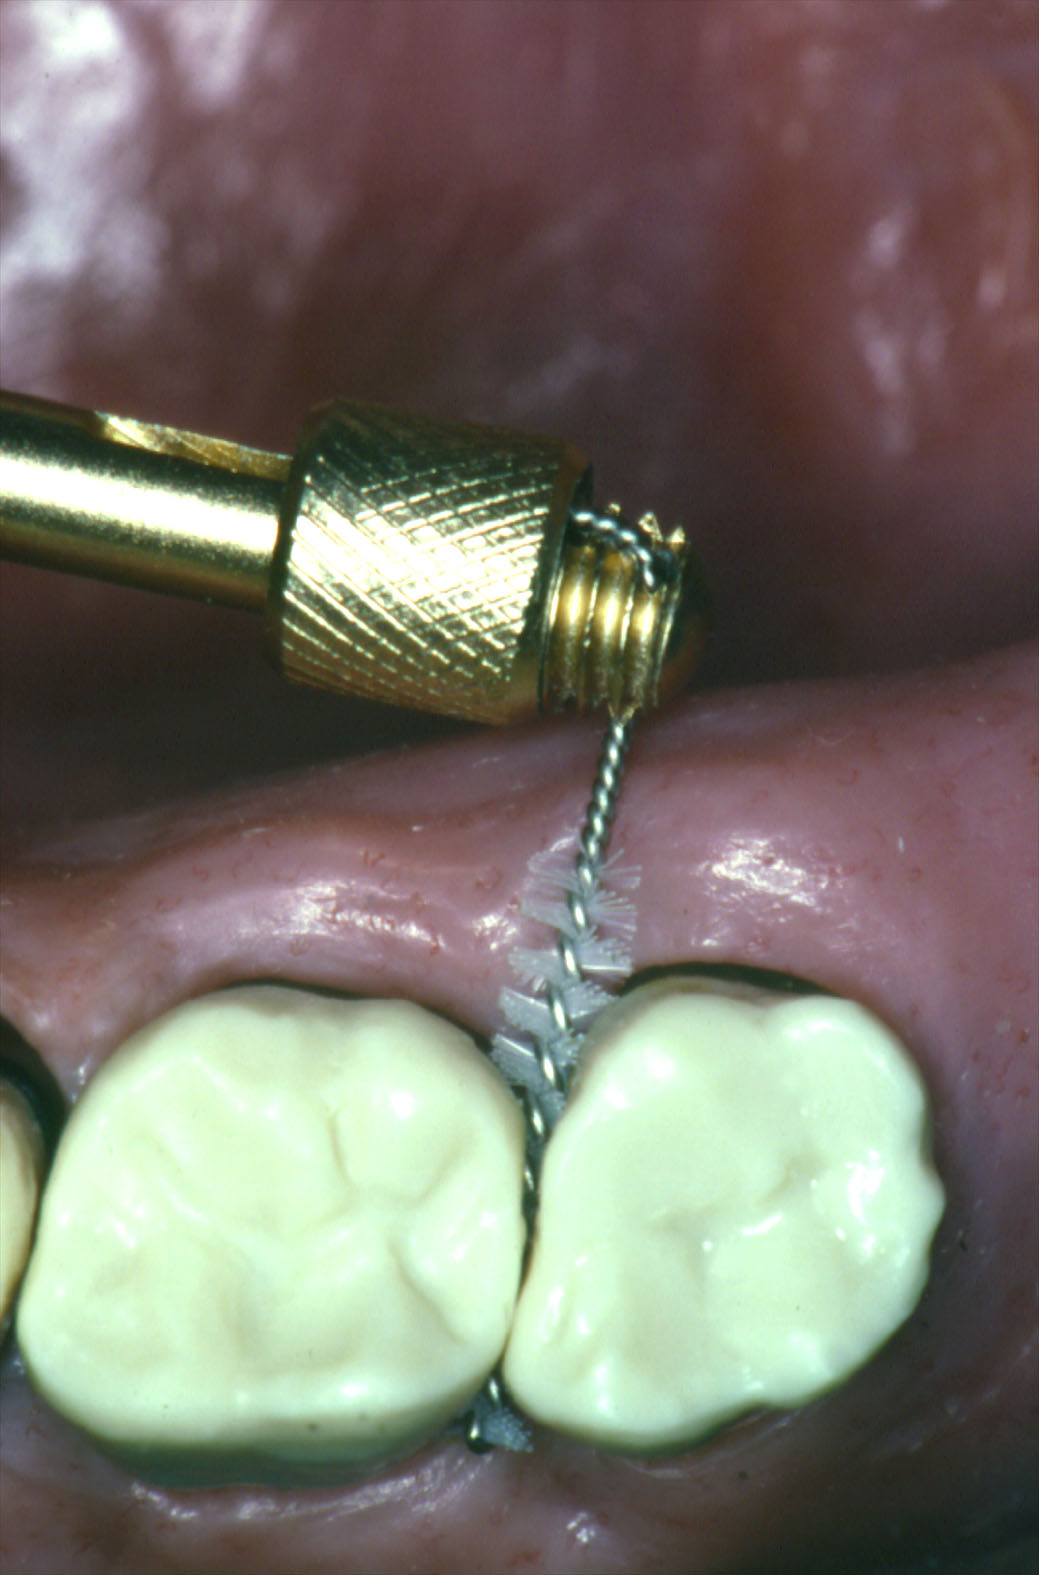

Ed allora fra le tante tecniche di spazzolamento vi proponiamo una “tecnica di compressione intrapapillare”, tecnica da me per tanto tempo insegnata all’Università di Bologna sotto il nome di terapia igienica, semplice e di facile esecuzione e basilare per ottenere un controllo efficace e veloce della malattia da parte del paziente.

Essa si basa sull’utilizzo per almeno 30 minuti/die, meglio di sera, di uno spazzolino interdentale chiamato anche proxabrush che, infilato fra un dente e l’altro, oltre a rimuovere la placca dale superfici dentarie, se premuto sulle gengive con movimento di fuori-dentro, riduce la tasca gengivale e conseguentemente il numero di germi ivi presenti.

- comprare ed utilizzare per almeno 30 minuti/die uno stimolatore interdentale di forma appropriata allo spazio presente, più piccolo nelle aree anteriori e più largo nelle zone posteriori, infilandolo fra i denti e massaggiando ripetutamente, spingendo lo stimolatore verso l’osso

- il movimento va eseguito dalle guance (vestibolarmente) verso la lingua e dalla lingua verso le guance